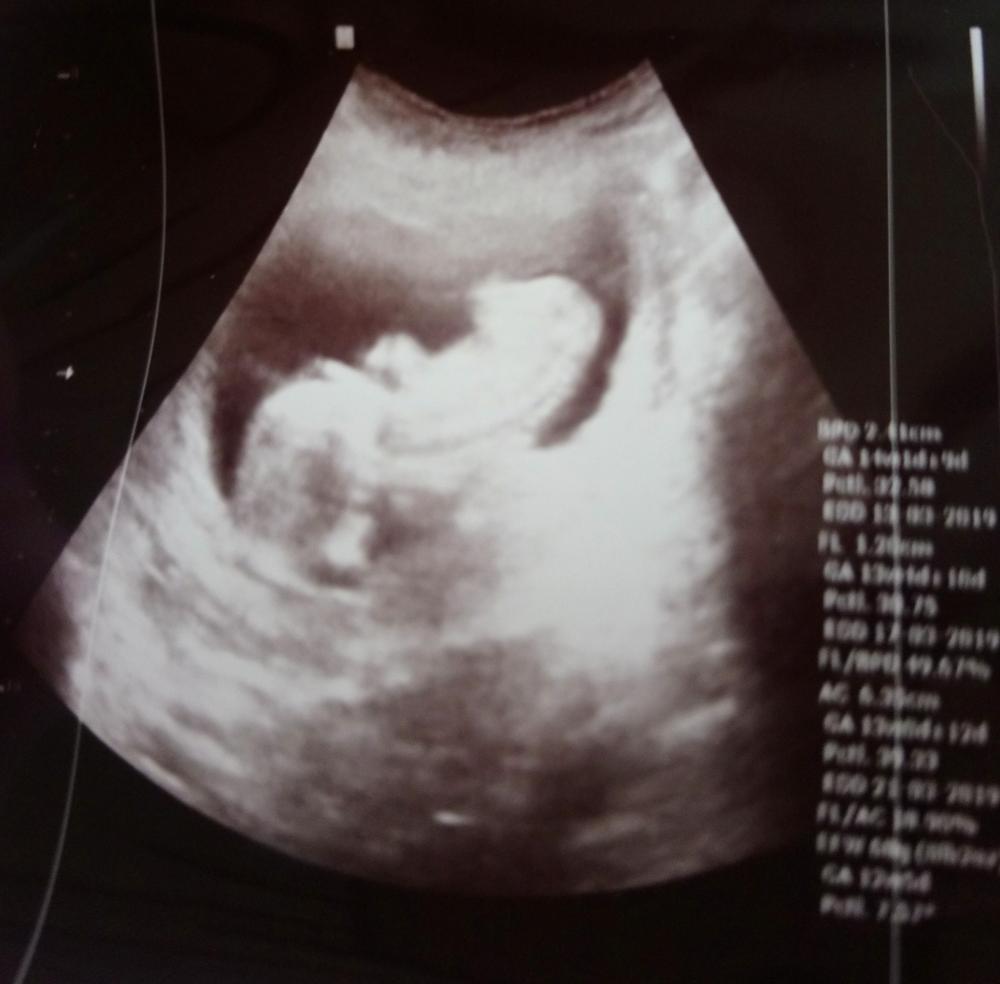

اليوم رحت عند الدكتورة عبير مشان تصرفلي الإبر وعملت سونار وقال ممكن ولد قبل مايقول زوجي لاتقولي انا بالأسبوع 13 رح نزل الصور كنت كتير فرحانة لاني شفتو عم يتحرك وصورتلي ياه رافع ايدو 😊

بنات شوفولي مبين شي خاصة قلبي قسى وبنت السلطنة احس عندكن خبرة